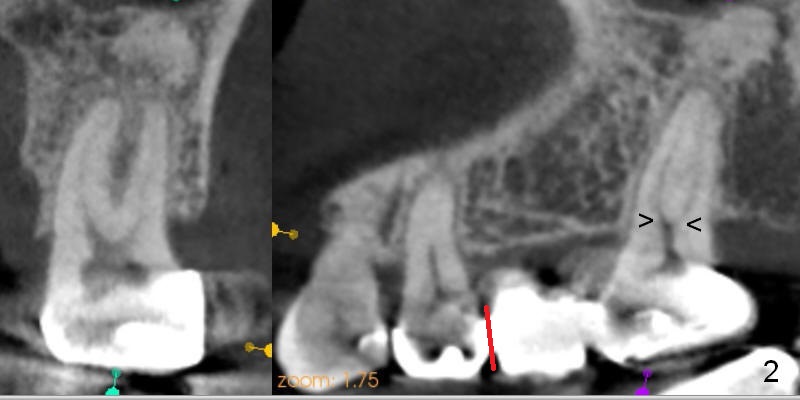

A 47-year-old woman complains of chewing pain at #15 after #30,31 implant placement.  It appears that there is mesial open margin (caries, Fig.1).  The bridge is to be sectioned at the junction between #13 and 14 (Fig.2 red line).  It is expected that #14 and 15 units will fall out by themselves.  Examine and remove caries at #15.  Conduct pulpal test and start RCT if there is time and necessity.  There is one common buccal orifice with two canals (Fig.2 arrowheads).  Be prepared for provisional for #15.  An implant will be placed at #14.